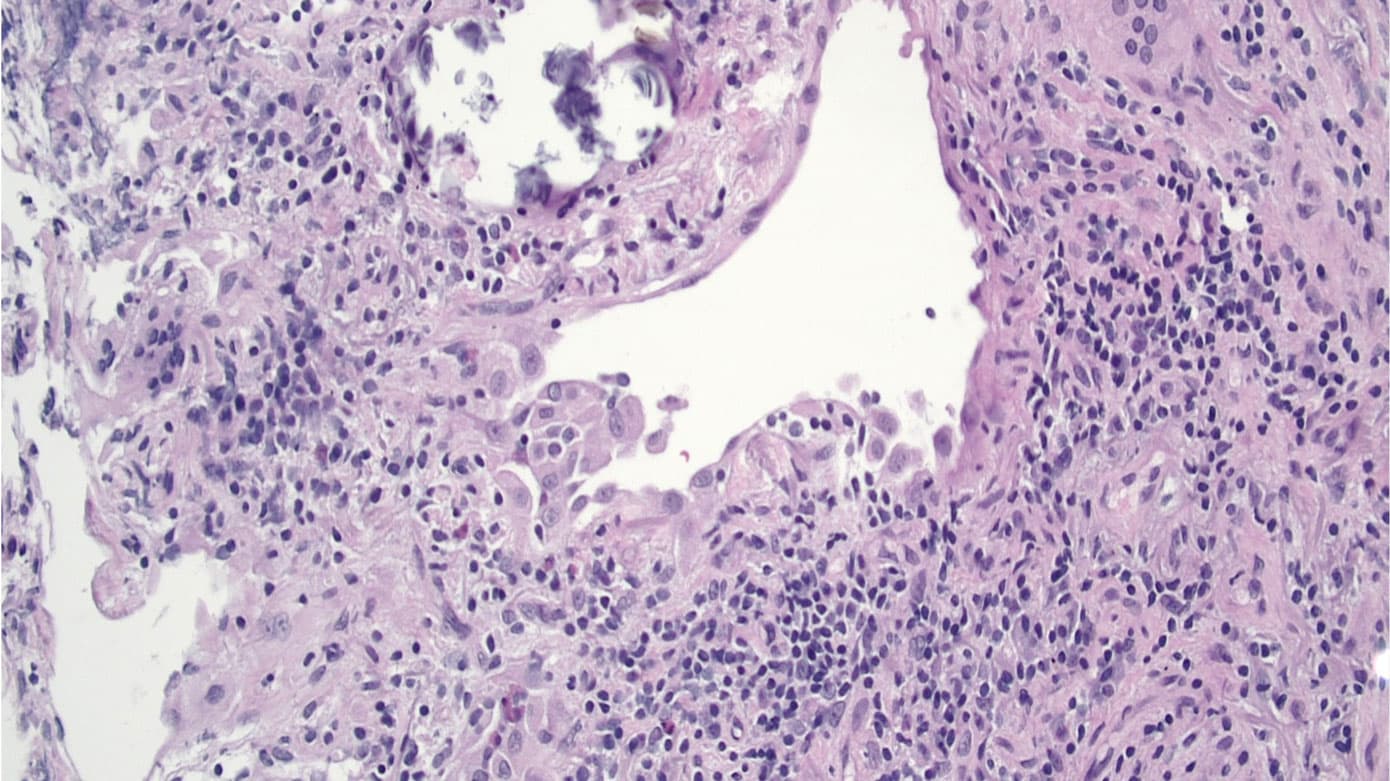

Histologisk ses interstitiel, lymfocytær infiltration især omkring bronkiolerne, cellulær kronisk bronkiolitis og svagt definerede nonnekrotiserende granulomer. Ved fibrotisk AA er disse træk kombineret med interstitiel og luftvejscentreret fibrose [18].